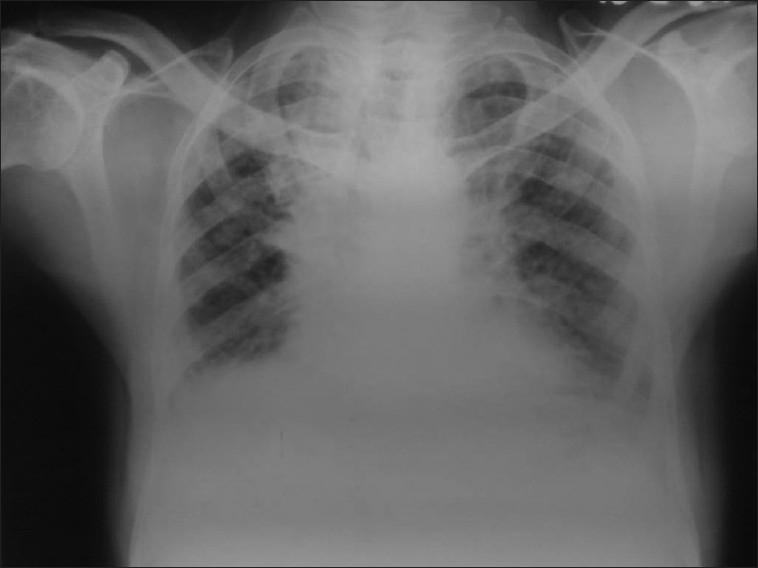

Diphenylhydantoin (phenytoin)-induced chronic pulmonary disease.

Drug-induced respiratory diseases are difficult to diagnose and therefore usually not identified, probably underestimated and under-reported. We report a case of diphenylhydantoin/phenytoin-induced chronic pulmonary disease in a 62-year-old male patient presenting with progressive dyspnea, eosinophilia, and pulmonary abnormalities. The importance of drug history in clinical history-taking and early diagnosis of drug-induced respiratory diseases is emphasized so as to prevent permanent pulmonary damage.

药物性呼吸道疾病难以诊断,因此通常未被识别,可能被低估且报告不足。我们报告一例62岁男性患者,因服用二苯乙内酰脲/苯妥英钠诱发慢性肺部疾病,该患者表现为进行性呼吸困难、嗜酸性粒细胞增多和肺部异常。强调了用药史在临床问诊及药物性呼吸道疾病早期诊断中的重要性,以预防永久性肺损伤。